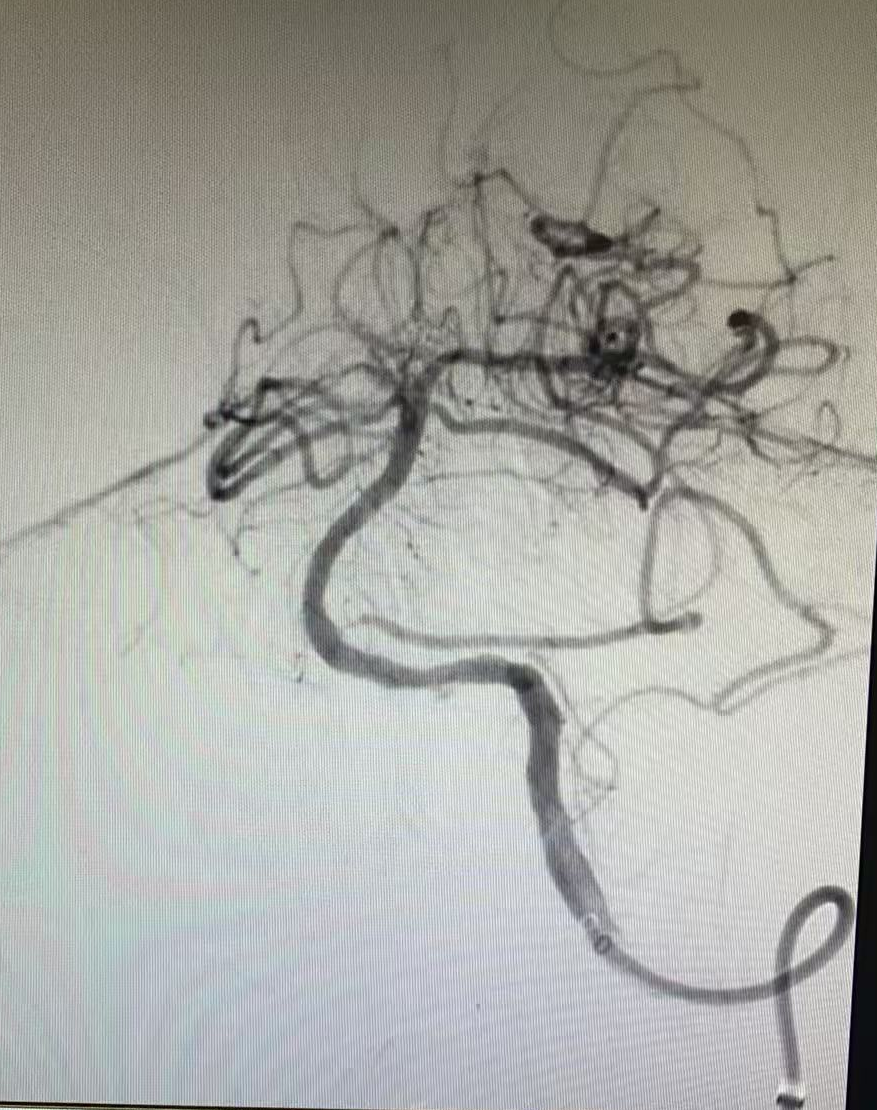

與家屬充分溝通并取得同意后,晚上7點42分,患者被推入介入手術(shù)室。手術(shù)團隊經(jīng)驗豐富,操作精準(zhǔn),晚上7點50分成功建立手術(shù)通路,在DSA影像引導(dǎo)下,微導(dǎo)絲與微導(dǎo)管精準(zhǔn)穿越閉塞血管段。晚上8點07分,堵塞的椎基底動脈被成功開通,從進入介入室到血管再通,僅用時25分鐘。

但挑戰(zhàn)還在繼續(xù),血管開通后發(fā)現(xiàn)內(nèi)部存在嚴重狹窄,遠端血流灌注不足,團隊隨即進行球囊擴張改善血流,但血管回縮明顯。為確保持久通暢,團隊果斷植入一枚支架。最終,血管形態(tài)恢復(fù)良好,血流達到最佳標(biāo)準(zhǔn),缺血的大腦獲得了充足的血液供應(yīng)。

術(shù)前血管閉塞

球囊擴張術(shù)后

支架置入后

一場集腦動脈造影、顱內(nèi)動脈取栓、球囊擴張與支架置入于一體的多模態(tài)手術(shù)順利完成。